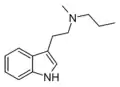

| MPT | artificial | H | CH3 | CH2CH2CH3 | N-Methyl-N-propyltryptamine | 850032-72-3 |

| DPT | artificial | H | CH2CH2CH3 | CH2CH2CH3 | N,N-dipropyltryptamine | 61-52-9 |